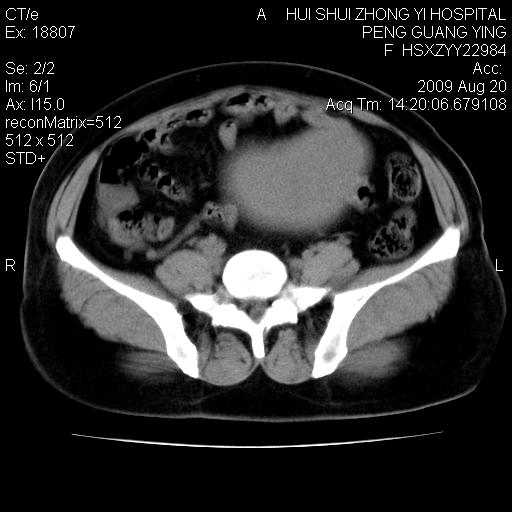

标题: CT21707:女,42岁,因发现下腹部包块2月。 [打印本页]

标题: CT21707:女,42岁,因发现下腹部包块2月。

增强看看,倾向于子宫肌瘤并囊变或腺肌征,宫腔少量积液。

病灶来源——子宫?附件?

从平扫角度看本人还是倾向于子宫肌瘤诊断,宫腔少量积液。

目前的影像表现显示肿块位于腹腔及盆腔,但具体定位,分清来源较困难,是否来源于卵巢、子宫无法定论,子宫直肠及子宫膀胱周围脂肪间隙尚较清晰,如果患者有过腹腔好或者盆腔手术史,也可以形成不典型的血中,最好手术后定为定性,我期待结果。

病史不全面,病灶来源可能是子宫或卵巢,若临床有剖腹产、痛经史,则更支持前者,亦更支持子宫腺肌症